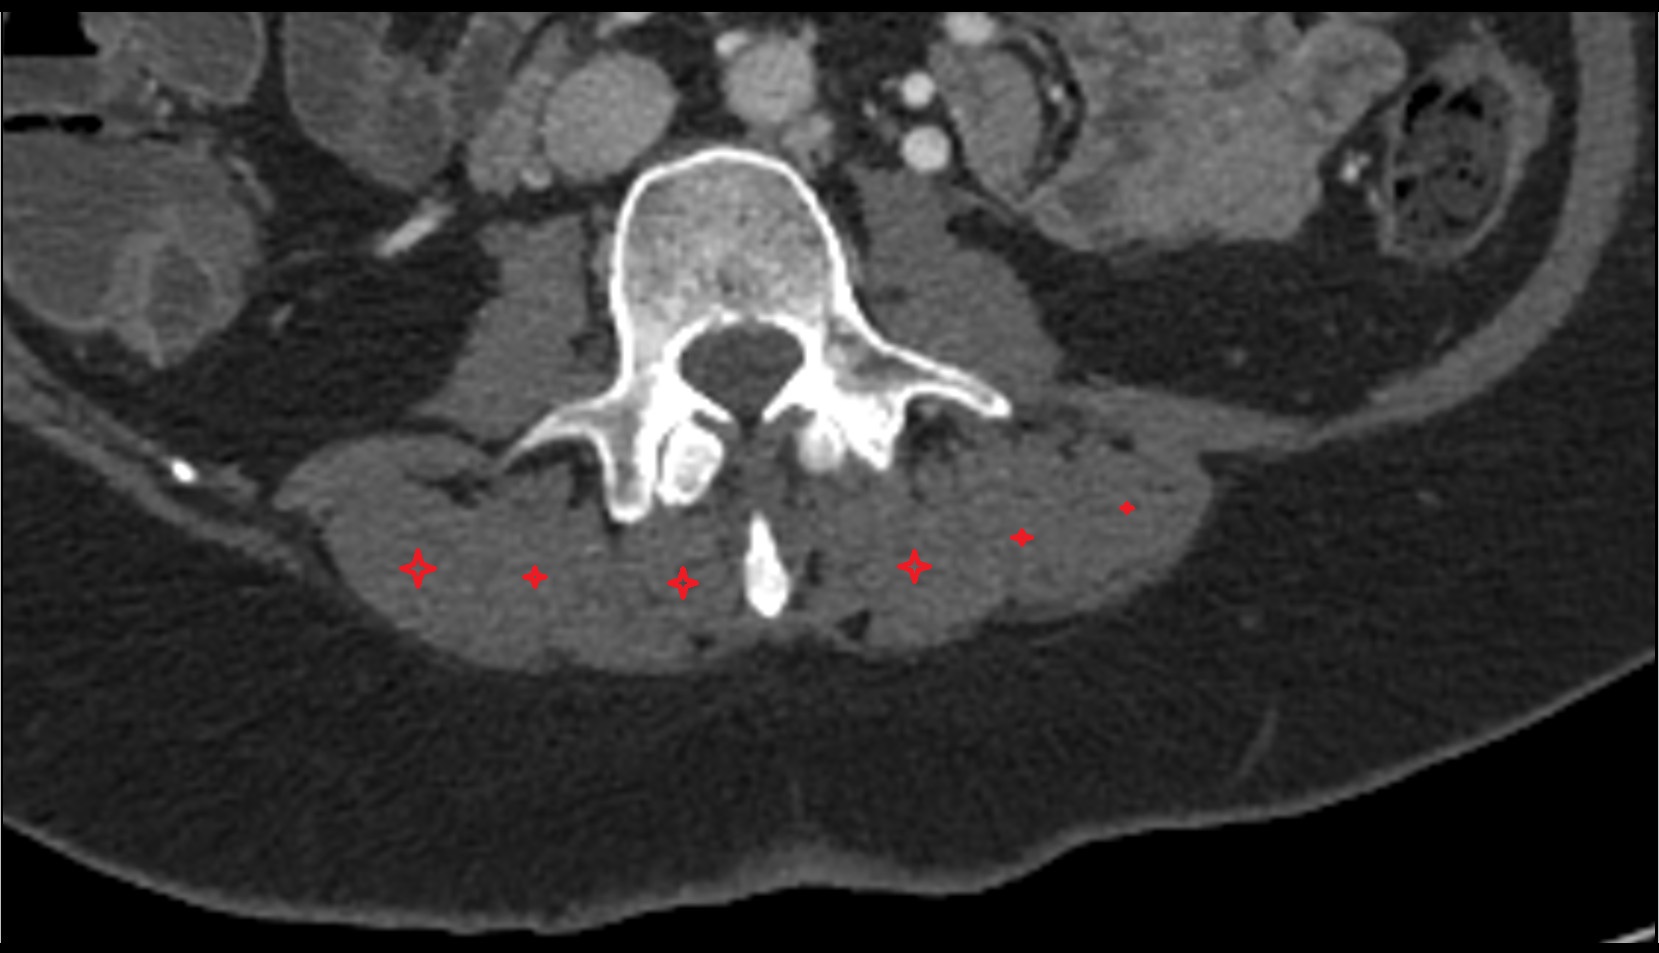

- Cauda equina

- Conus medullaris

- L5–S1 Intervertebral disc

- L4–L5 Intervertebral Disc

- L3–L4 Intervertebral Disc